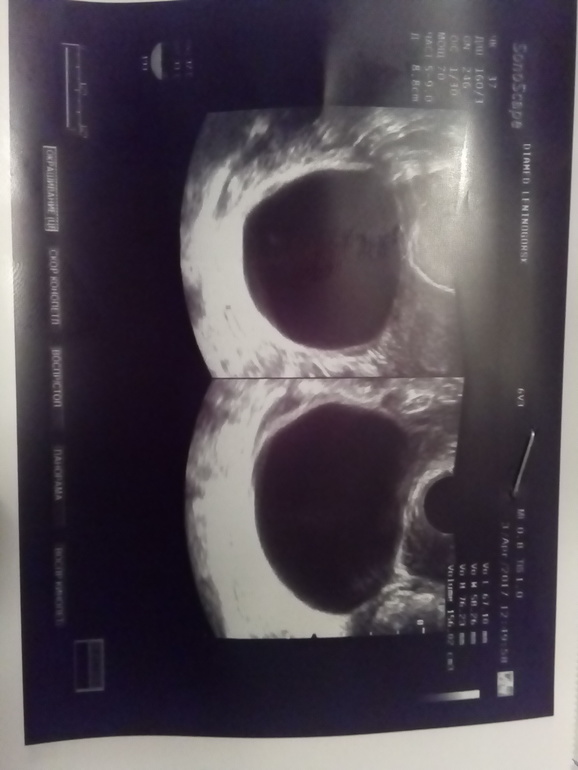

УЗИ повторное 9 дц

Девочки, обьясните, страшно ли это? Киста п.я. 67 мм,, а в левом поликистозное изменение.? Эндик ваще 5 ...Что это значит.